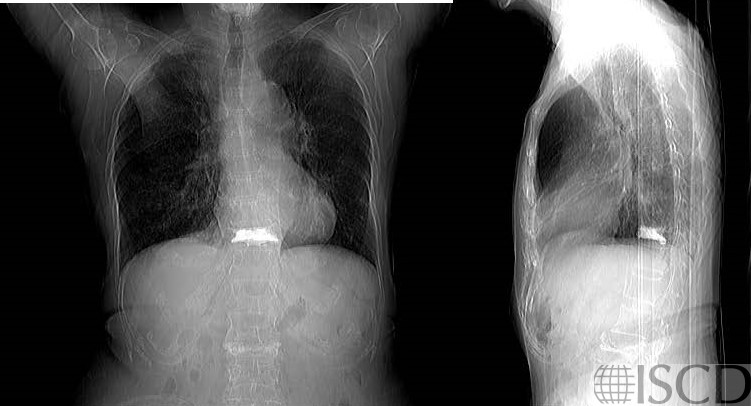

There is vertebral augmentation at L3.

The accompanying PA and lateral chest radiograph also shows the vertebral augmentation.

There is vertebral augmentation at L3 that is also seen on the accompanying chest radiograph.